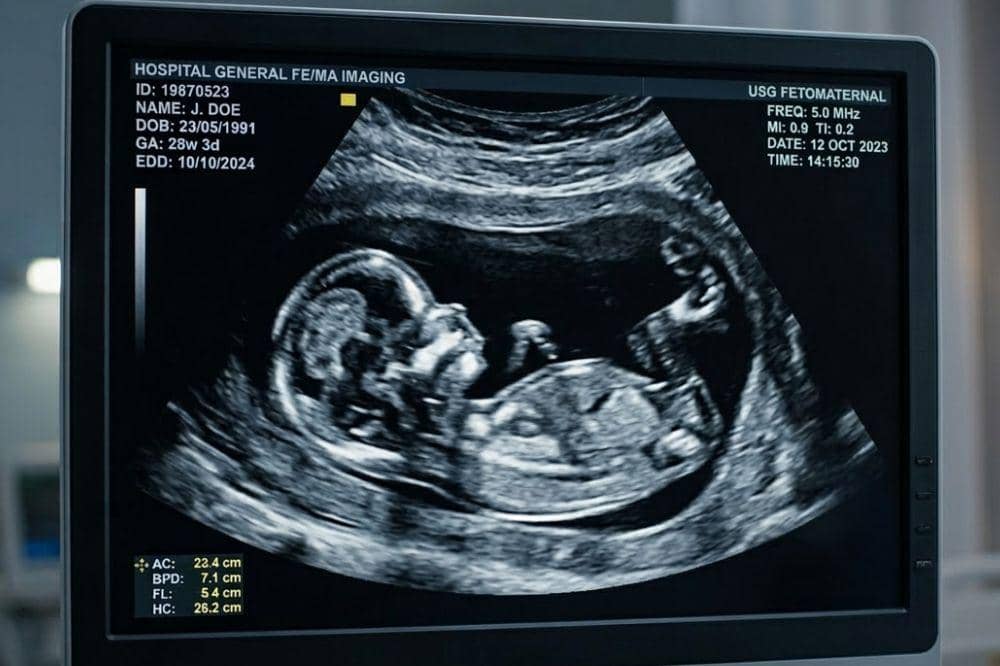

USG fetomaternal digunakan untuk mendeteksi kelainan janin sejak dini dengan pemeriksaan lebih rinci.

Untuk mendeteksi kelainan pada janin sejak dini, digunakan pemeriksaan USG fetomaternal. USG ini dilakukan untuk menilai kondisi janin secara lebih rinci, termasuk mengetahui kemungkinan adanya kelainan bawaan sejak awal kehamilan. Agar hasil pemeriksaan lebih akurat, USG fetomaternal sebaiknya dilakukan pada waktu-waktu tertentu selama kehamilan yang telah dianjurkan.

Selama kehamilan, ibu hamil umumnya menjalani pemeriksaan USG 2D, 3D, atau 4D. Pemeriksaan ini digunakan untuk memantau kondisi serta perkembangan janin di dalam kandungan, seperti melihat pertumbuhan janin, memeriksa detak jantung, hingga memperkirakan usia kehamilan dan waktu persalinan.

Berbeda dengan itu, USG fetomaternal merupakan pemeriksaan yang lebih spesifik. Tujuan pemeriksaan ini adalah untuk mendeteksi lebih awal kemungkinan kelainan pada janin maupun kondisi tertentu yang dapat memengaruhi kesehatan ibu hamil.

Pemeriksaan fetomaternal biasanya dilakukan secara lebih mendalam dibandingkan USG biasa. Melalui pemeriksaan ini, dokter dapat menilai struktur tubuh janin dengan lebih rinci sehingga jika terdapat kelainan, kondisi tersebut dapat diketahui lebih cepat dan penanganan dapat dipersiapkan sejak dini.